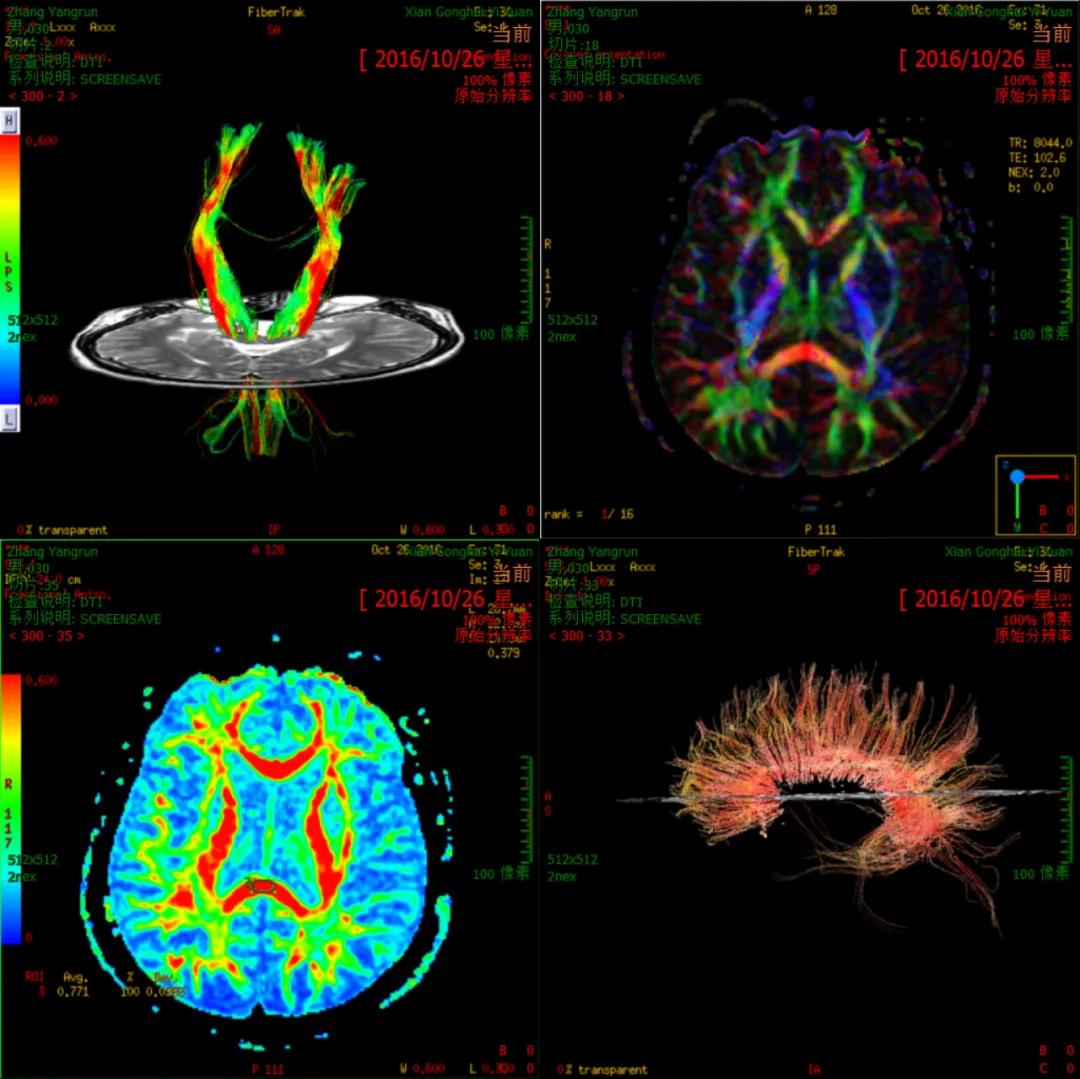

脑功能成像

(DTI)